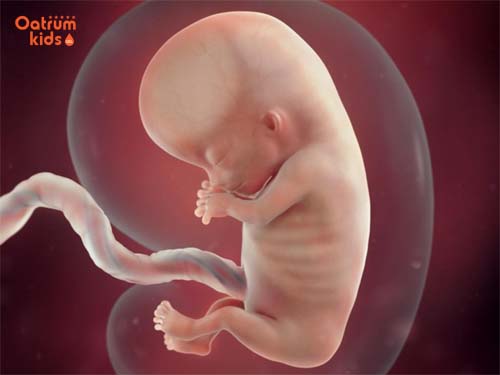

Các chuyên gia cho rằng trong tuần thai thứ 11 sự phát triển nổi bật nhất của con so với tuần thứ 10 đó là bé đã bắt đầu phát triển khả năng phản xạ. Mẹ biết không, lúc này con yêu đã có thể xòe đôi bàn tay nhỏ bé của mình ra rồi nắm lại như nắm đấm.

Bên cạnh đó các ngón chân cũng co lại, mặc dù cơ mắt nhắm chặt nhưng bé vẫn có thể đưa ngón tay cái lên miệng rồi mút. Chân bé có thể có các động tác giống như đang đạp, bé vặn mình và xoay mình, tuy nhiên do bé còn nhỏ nên mẹ chưa cảm nhận rõ.

Thai nhi ở tuần thứ 11 đã hình thành phản xạ, đưa tay lên miệng.

Cũng trong giai đoạn thai nhi tuần thứ 11 bộ phận ruột của bé phát triển rất nhanh, thậm chí ruột cũng bắt đầu được sắp xếp đúng vào khoang bụng của bé. Kèm theo đó là thận cũng đã bắt đầu hoạt động bài tiết nước tiểu vào bên trong bàng quang của bé.

Một điểm rất quan trọng nữa đối với sự phát triển của thai nhi 11 tuần tuổi đó là lúc này các tế bào thần kinh của bé yêu cũng được nhân lên rất nhanh. Cụ thể là các khớp thần kinh đã được hình thành ở trong não của bé để tạo nền tảng hoàn chỉnh về sau.

Hơn nữa trong thời điểm này khuôn mặt của con yêu đã rõ hơn, hình dạng trông bắt đầu giống như khi bé ra đời. Đồng thời mắt của bé cũng đã di chuyển từ 2 bên vào đúng giữa khuôn mặt, tai cũng đã ở đúng vị trí.

Lúc này tính từ đỉnh đầu đến chóp mông bé sẽ dài tầm khoảng 5cm, kích thước của bé gần bằng một trái chanh và nặng chừng 15g. Hoạt động chủ yếu của bé ở giai đoạn 11 tuần tuổi là đá chân,vận động không ngừng, trườn và xoay người… Sau càng lớn dần bé sẽ thực hiện các động tác này nhiều hơn và thường xuyên hơn.